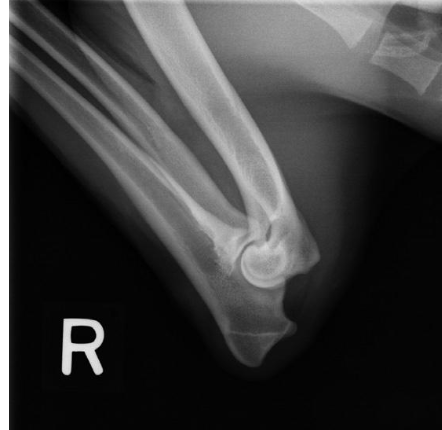

what radiographic view of the elbow is shown?

lateral view with elbow fully flexed

what structure of the elbow is focused on if we are doing a lateral view with the joint fully flexed?

olecranon process